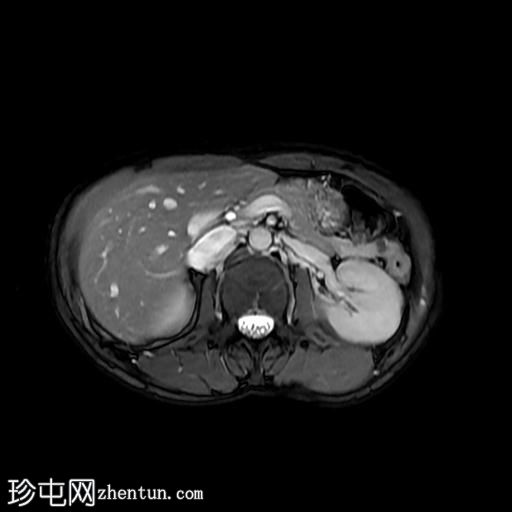

轴位T1加权像

C+脂肪抑制像

8.jpeg

此外,肝脏第二段左叶可见一 10 x 12 mm 的肝脏肿块,在重 T2 加权像上呈高信号。该病灶呈周边结节状强化,提示为血管瘤。肝脏第八段右叶可见一类似病灶,大小约 10 mm。

此外,右肾中极可见一大小约 5 mm 的肾皮质囊肿。